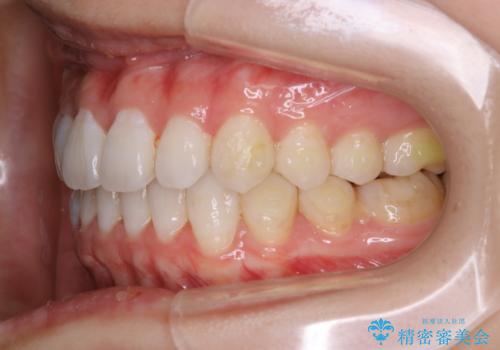

- インビザライン(マウスピース矯正)の治療中にステインが気になり、クリーニング希望とのことでした。

アタッチメントの周囲などに、ステインの付着や、プラークがみられたためPMTC(自費クリーニング)30分コースを行いました。

矯正治療中は、虫歯や歯周病のリスクが高くなったり、長い時間マウスピースを着用することにより、ステイン(着色)がしやすくなることがあります。

そのため矯正治療中は、(マウスピース矯正・ワイヤー矯正共に)クリーニングを行い、こまめに汚れを取り除き、お口のケアをすることが大切です。